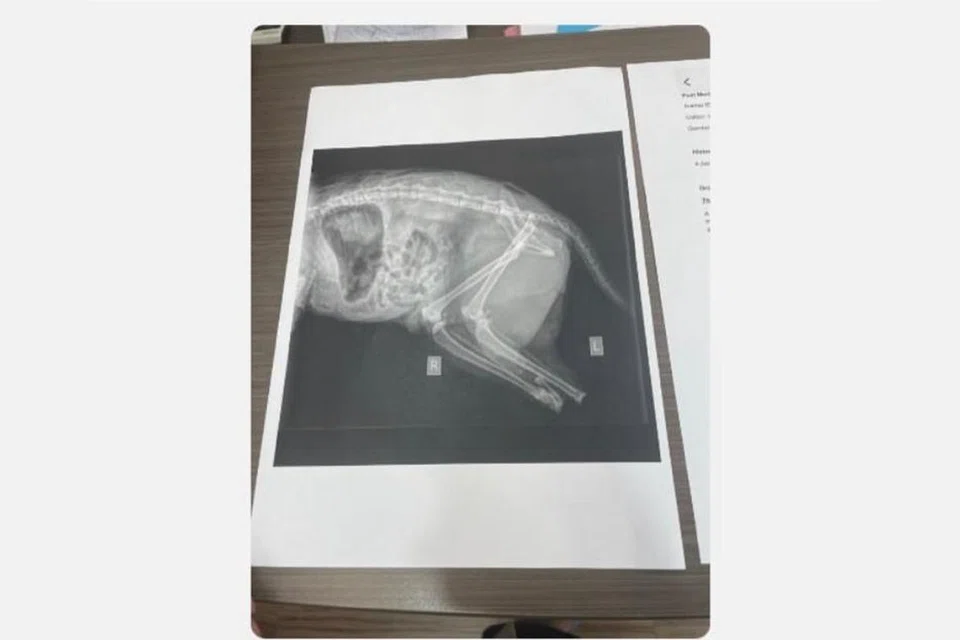

Bagaimanapun, seorang pengguna media sosial pada 23 Disember berkongsi pendedahan seorang doktor haiwan swasta yang menunjukkan laporan bedah siasat terhadap kucing berkenaan, dengan mendakwa terdapat kesan menunjukkan anggota badan haiwan berkenaan telah sengaja dipotong.

Presiden Persatuan Haiwan Malaysia, Encik Arie Dwi Andika, pula menjelaskan beberapa kucing yang terbunuh mempunyai kesan jenayah dan clean cut (kesan potongan sempurna) pada bangkai haiwan yang dijumpai dan pakar veterinar berpendapat luka yang ada tidak menggambarkan serangan anjing liar.